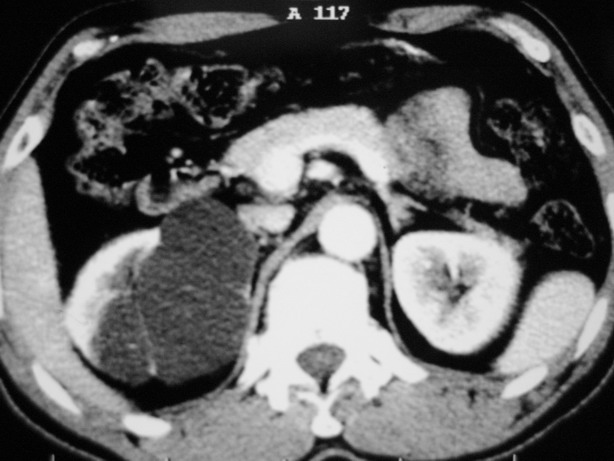

增强:

肾盂旁多囊性占位,有实性成分,增强有轻度强化,收集期病变内无造影剂显影。诊断肾盂旁囊肿,有实性成分无法解释,查书后诊断为:多房性囊性肾瘤!!不知大家同意否?????????对本病知道不多,望大家不吝赐教!!